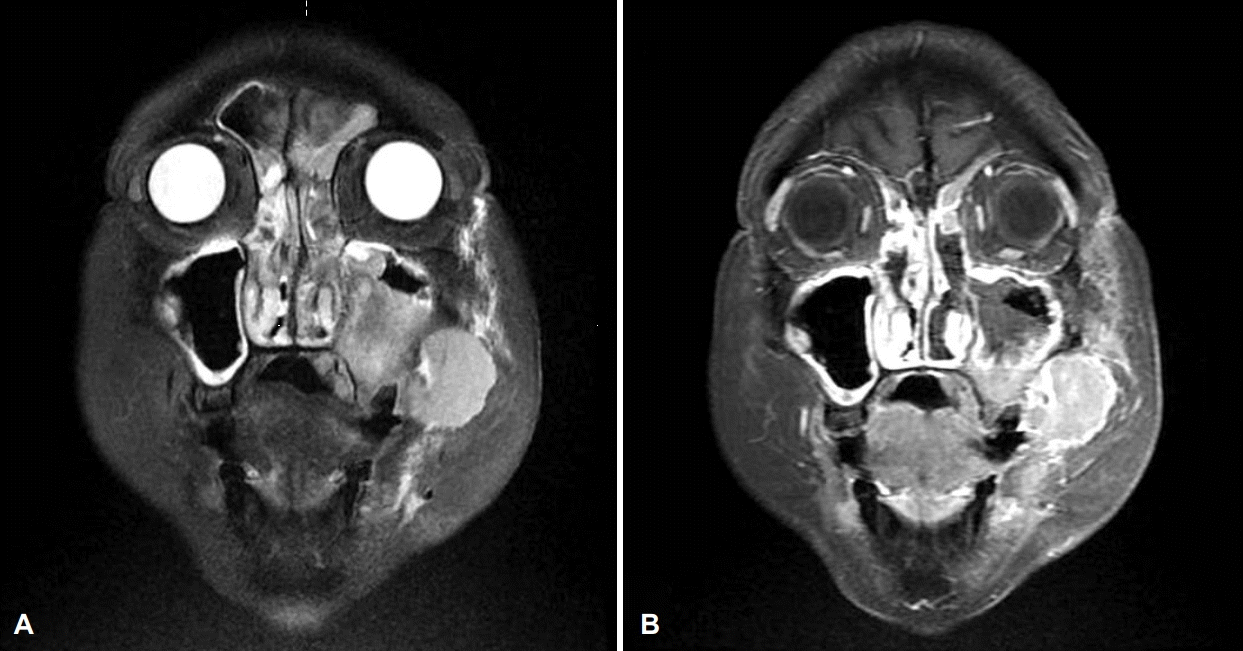

술 후 당일 시행한 조영 증강 경부 전산화단층촬영에서 좌측 상악동, 상악동 앞쪽 부위 및 협부 점막에 걸쳐 조영이 증강되는 5.5 cm 연조직 종괴가 관찰되었고(Fig. 4A), 좌측 측경부와 인두후부에 다수의 림프절 전이 소견이 관찰되었다(Fig. 4B). 조영 증강 부비동 자기공명영상촬영에서는 동일 부위에 T2 강조영상에서 중간 신호 강도를 보이고(Fig. 5A), T1에서 저신호 강도를 보이며, 조영제를 사용한 T1 강조영상에서 조영 증강되는 연조직 종괴를 확인하였다(Fig. 5B). 술 후 5일째 시행한 양전자방출단층촬영에서 좌측 상악동, 전상악동 부위, 협부 점막 및 좌측 경부 림프절(Fig. 6A)에 fluorodeoxyglucose 섭취 증가와 함께 간과 비장(Fig. 6B)의 전이 의심 소견이 보였다. 폐의 우상엽 부위에는 수술 당일 조영 증강 경부 전산화단층촬영에서 보이지 않고 새롭게 관찰되는, 염증성 결절 의심 소견이 있어 조영 증강 흉부 전산화단층촬영을 추가로 시행하였고, 양성 병변이나 전암성 병변배제 위해 3개월 뒤 추적 관찰을 권유받았다. 이에 최종 좌측 상악동에서 기원한 폐외소세포암(cT4aN2bM1)으로 진단되었다. 이후 환자가 원하여 항암 치료를 위해 타 병원으로 전원되었다.

Post-operative coronal paranasal sinus MR T2 weighted (A) and T1 enhanced (B) images. T2 weighted coronal image shows 5.5 cm soft tissue lesion with intermediate signal intensity involving left maxillary sinus and buccal region (A), and gadolinium-enhanced T1 weighted coronal image shows enhanced soft tissue mass in the same region (B).